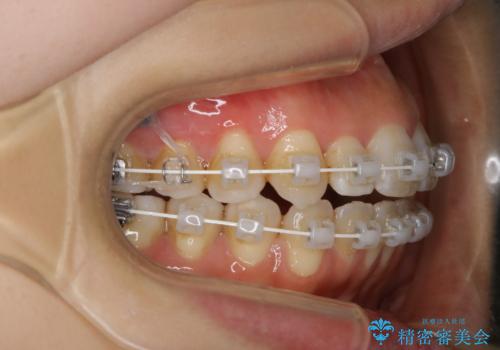

- ワイヤー矯正 審美装置

インビザラインの方法でも治せる患者様でしたが、希望によりワイヤー矯正となりました。

インビザライン治療では奥歯の圧下が問題なく行えますが、ワイヤー治療ではマイクロインプラントを使用しなければ奥歯の圧下を行うことが難しいです。